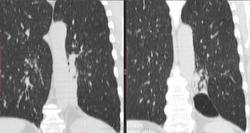

обработка, 2012г:

КТ:

Добавила КТ в начале случая. Контрастирования не было, не будет. Дайком тут: http://files.mail.ru/0KS7TD   22,3 МБ объём

По всей видимости аномалия развития, связанная с нижней долей слева по типу гипоплазии-недоразвития.

Сейчас и на рентгенограмме левый корень выглядит ущербно недоразвитым в области тела и хвоста, да и обнажение части грудного отдела позвоночника справа моежт быть объяснимо.

Выставила интралобарную секвестрацию. Пациент консультирован в областном центре, дополнительных методов обследований там не выполнялось, посмотрели дайком нативной КТ ОГК и согласились.

При просмотре ФЛГ видела кисты/буллы и ненормальный левый корень. Полосу за тенью сердца приняла за шварту. Взяла на КТ, чтоб разобраться, связан ли куцый корень и кисты. Секвестрация оказалась сюрпризом. Решила, что всё-таки аномалия со своей плеврой. Насколько смогла разобраться на нативном исследовании, все бронхи на месте, а дополнительное образование с кистами и каким-то зачатком бронхиальной системы - ниже S6 и медиальнее S10. С темой секвестрации знакома по детским случаям коллег.